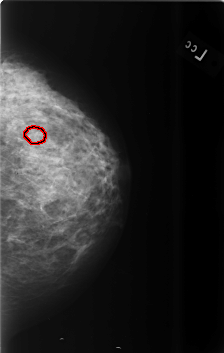

B_3470_1.LEFT_CC

LEFT_CC LINES 5648 PIXELS_PER_LINE 3576 BITS_PER_PIXEL 12 RESOLUTION 50 OVERLAY

FILE: B_3470_1.LEFT_CC.OVERLAY

TOTAL_ABNORMALITIES 1

ABNORMALITY 1

LESION_TYPE CALCIFICATION TYPE PLEOMORPHIC DISTRIBUTION CLUSTERED

ASSESSMENT 4

SUBTLETY 3

PATHOLOGY BENIGN

TOTAL_OUTLINES 1

BOUNDARY